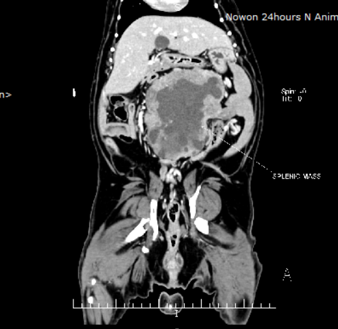

강아지 비장이 파열된 상태로 내원하였어요. 강아지 비장파열 검사와 수술 : 네이버 블로그